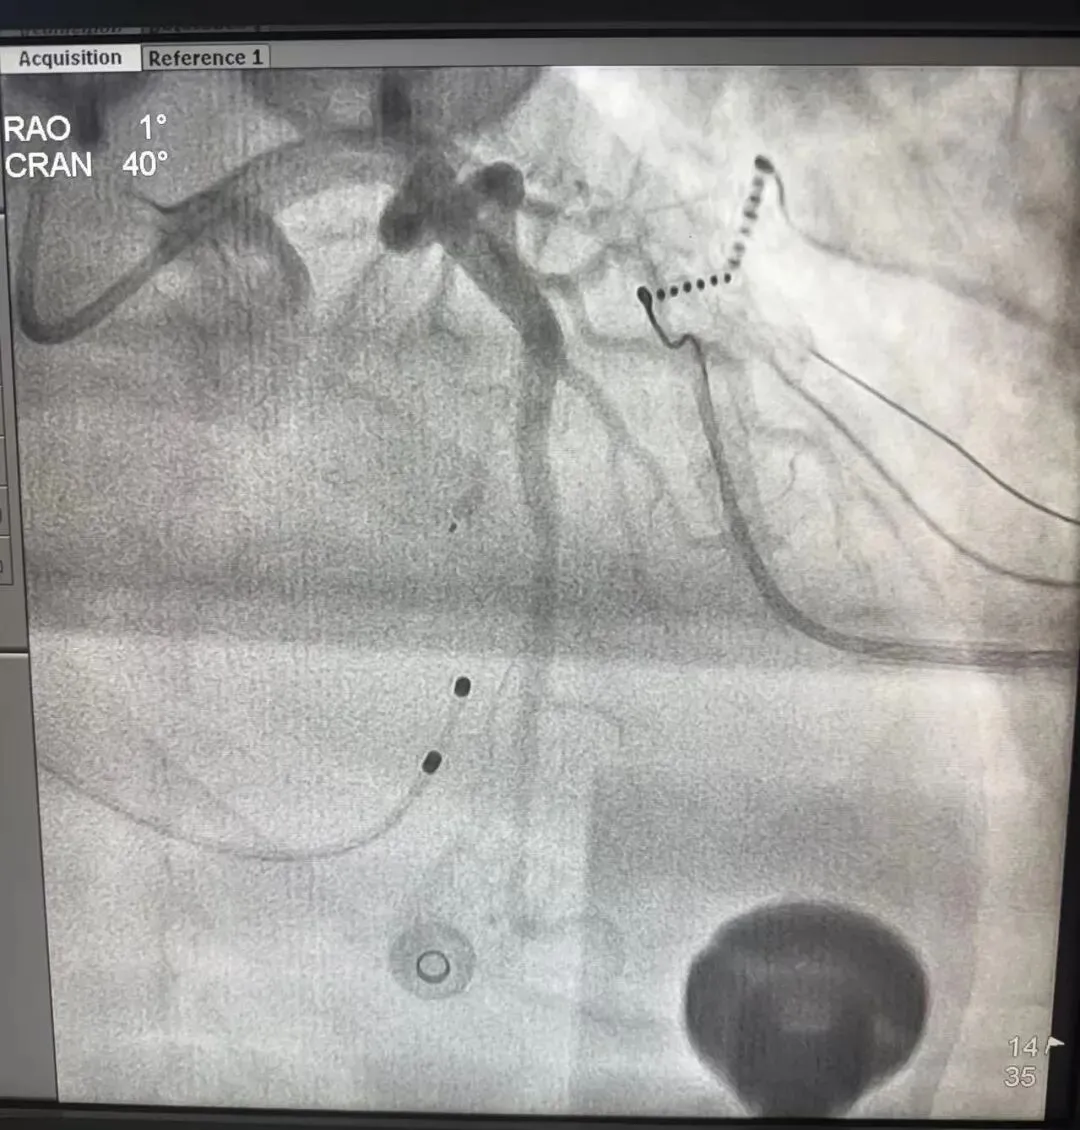

心血管内科主任王瑞华团队凭借丰富的经验和精湛的技术,通过冠状动脉造影精准定位,仔细评估患者的室间隔支血管条件,采用心肌声学造影,心腔内超声及三维标测,确定拟消融的间隔支动脉支配肥厚梗阻的基底部室间隔。根据室间隔支动脉的供血范围,精细操作,密切观察术中心电及压力变化,间隔支注入2ml无水酒精。

术中精准定位靶血管,OTW球囊扩张,无水酒精化学消融

术后即刻测量显示,患者左室流出道压力阶差显著下降,手术取得预期效果。患者术后感受良好,生命体征平稳,当日即可下床活动,胸闷气短症状得到明显缓解。